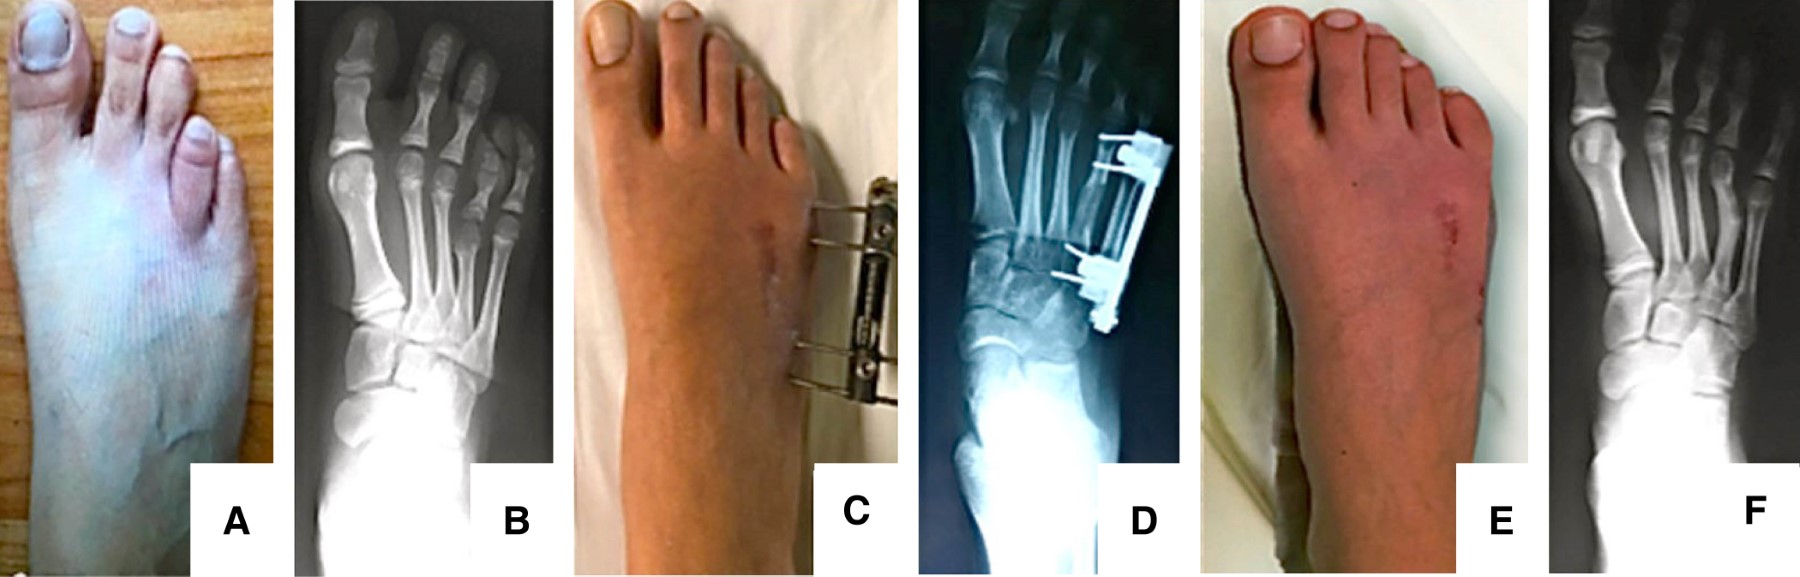

Functional and radiographic effectiveness of congenital brachymetatarsia treatment

Brachymetatarsia is a congenital or acquired malformation, which includes an abnormal shortening of one or more metatarsals. The objective of this study was to evaluate the functional and radiographic results of surgical treatment in congenital brachymetatarsia with lengthening osteotomy and use of external fixation. Material and methods: A retrospective, descriptive, cross-sectional and analytical study was conducted at the Shriners Hospital for Children, Mexico City, between January 2011 and December 2014. Patients from 10 to 18 years of age with congenital brachymetatarsia, aesthetic disagreement, complete functional and radiographic evaluation of the affected foot, undergoing progressive distraction with external minifixation of the affected metatarsal, with a minimum follow-up of five years were included. For the functional evaluation, the MOXFQ questionnaire was used. For the radiographic evaluation, the elongated millimeters, the consolidation time in each affected metatarsal were taken into account, without obviating the complications obtained. Results: 14 patients were included, 23 affected metatarsals; 1 man (8%) and 13 women (92%). The average age was 14 years old. In 69% both feet were affected, 22% right foot and 9% left foot. The fourth metatarsal was the most affected. The three sections evaluated in the MOXFQ questionnaire improved by more than 50%, with greater predominance in the category of social interaction. Radiographic evaluation showed a growth rate of 40% with an average consolidation time of 16 weeks. Both statistically significant evaluations. Eight patients presented complications (34%). Conclusion: The lengthening and external fixation osteotomy continues to be effective as a therapeutic option for brachymetatarsia, obtaining in this work, improvement of functional and radiographic results after treatment with statistically significant results. The percentage of complications found were similar to that reported in other studies despite having a high average growth rate.

Figure 1

Figure 2